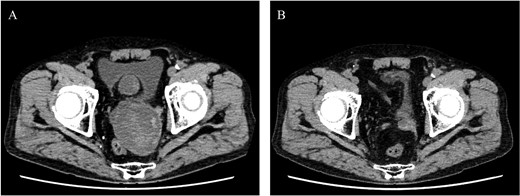

An 80-year-old female was admitted for the expansion of a left CIAA and IIAA. Ten years prior, she had undergone coiling of peripheral branches of the IIAA and stent graft placement in the CIAA. Contrast-enhanced CT showed the IIAA and CIAA extending into the deep pelvis. The maximum short diameter was 90 mm, and there were no signs of endoleak (Fig. 4).

Preoperative computed tomography imaging showing a left common iliac artery aneurysm and internal iliac artery aneurysm with a maximum short diameter of 90 mm. A—Axial image, B—3D image. LCIAA, left common iliac artery aneurysm.

She underwent surgery under general anesthesia. A midline abdominal incision and an intraperitoneal approach were employed. The retroperitoneal space was accessed from the lateral side of the sigmoid colon to reach the CIA. The aneurysm was incised midway. The hematoma and coils were removed, and the stent graft was observed. The laparoscope was utilized to inspect areas obscured from direct view, such as behind the stent graft, to confirm that no type I or IIIb endoleak was present (Fig. 5). A type II endoleak was observed near the proximal neck of the stent graft, which was thought to be the cause of the aneurysm expansion. The IIAA was sutured with 3–0 monofilament, and the aneurysm was closed. The left ureter was close, and care was taken during suturing to avoid including it in the stitches. The operation took 177 min, and the patient was discharged on the tenth day postoperation. Follow-up CT at 7 months postoperation showed a reduction in aneurysm size (Fig. 6).

Postoperative computed tomography showing a reduction in aneurysm size. A—Preoperative image, B—7-month postoperative image.